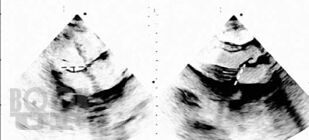

Методическое пособие посвящено одной из важнейших патологий современной кардиологии — первичному пролапсу митрального клапана и его роли в популяции. Подробно представлены основные патологические процессы, приводящие к развитию пролапса, его последствия для сердца, варианты лечения, до и послеоперационного ведения пациентов.

Особое внимание уделено эволюции критериев пролапса митрального клапана, использованию алгоритмов, исключающих гипердиагностику самой аномалии и сопутствующих осложнений. Так как основное значение в прогнозе заболевания имеет степень регургитации на клапане, которая может возрастать при физической нагрузке, обсуждаются вопросы проведения нагрузочных тестов с эхокардиографией, а также варианты допустимой физической активности пациентов.

Издание содержит многочисленные рисунки и схемы, иллюстрирующие расстройства гемодинамики, результаты исследования сердца и современные оперативные вмешательства при данной патологии.